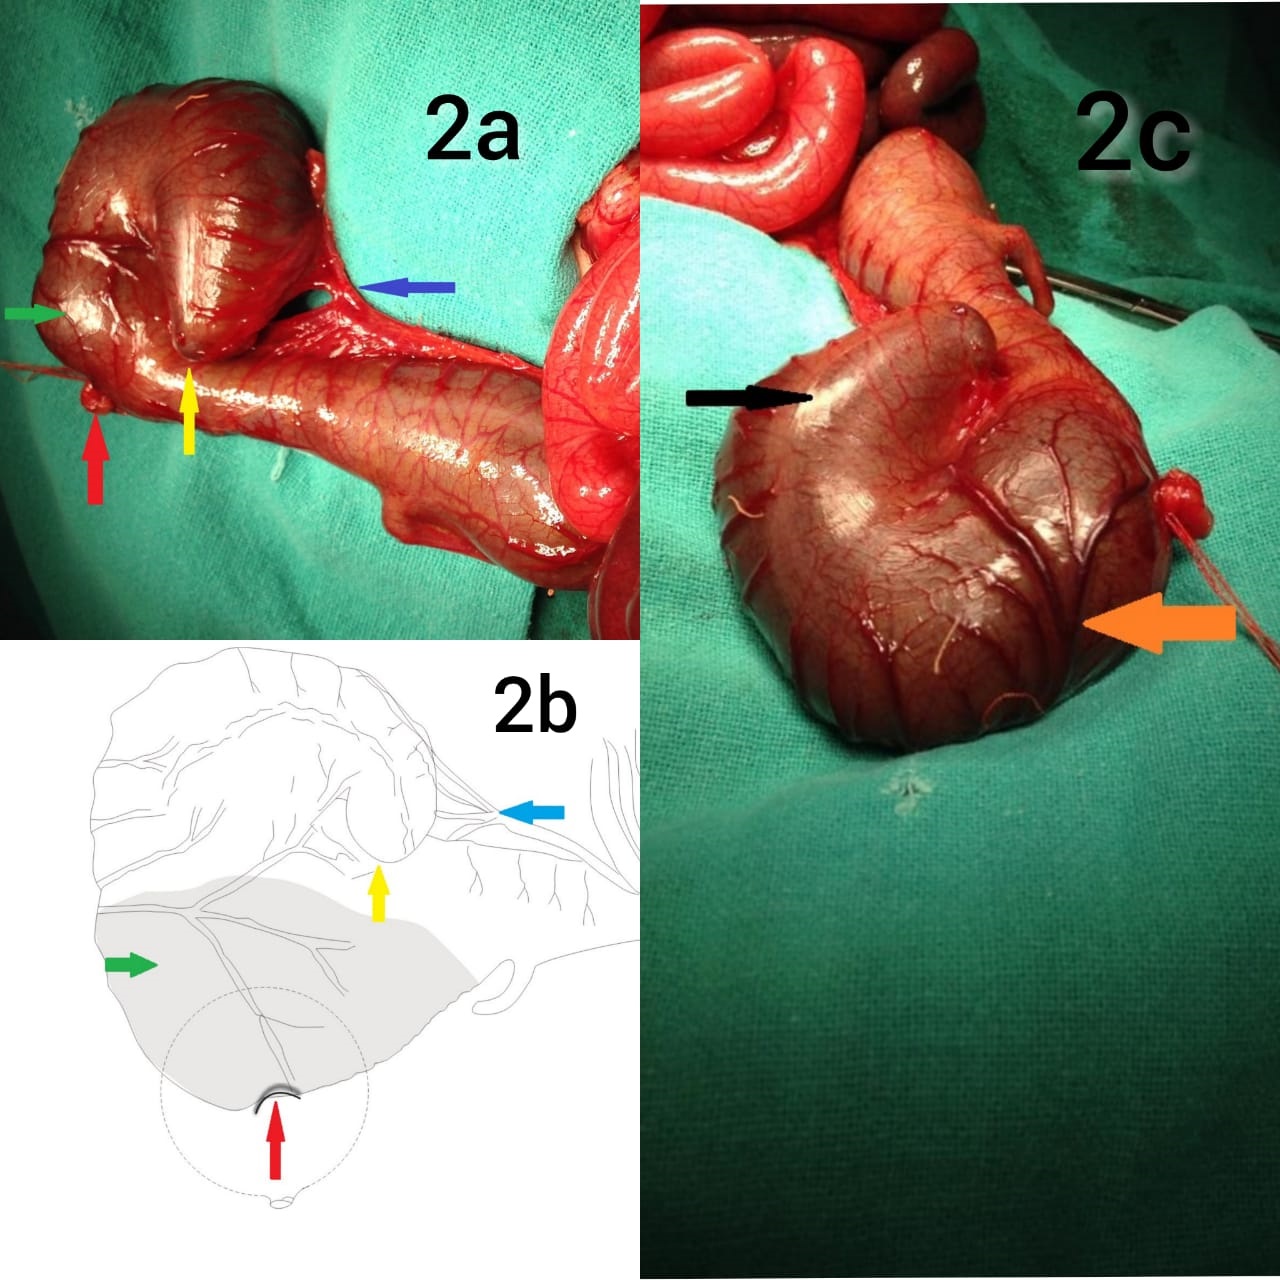

After preoperative optimization, laparotomy was performed via left “hockey stick” incision, and ileum was seen opening into caecum; which in turn opened into a colonic pouch measuring 12×10×10 cm; and the diagnosis of CPC was confirmed (Fig2a, 2b-shaded area.). This pouch continued distally into a normal bowel (Fig. 2a, 2b-non-shaded area); which had distinct taenia coli and normal vasculature; but ended abruptly; with a V-shaped mesenteric defect (colonic atresia type III a) (Fig. 2c). The proximal part of the dilated colon lacked haustrations, taenia coli and appendices epiploicae, had abnormal vasculature; and had a fistulous communication with the urinary bladder (Fig. 2c). Ligation of colovesical fistula and excision of the atretic colon along with colonic pouch and ileocecal junction and; an end ileostomy was performed. The postoperative period was uneventful.

Figure 2

a) Image of resected specimen b) line diagram showing congenital pouch colon (green arrow) with divided genitourinary fistula (red arrow); terminating into an atretic colon (yellow arrow) with a mesenteric defect (blue arrow) c) image of the resected specimen showing distinct taenia coli in the atretic segment (black arrow) and; thickened and abnormal vasculature of pouch colon (orange arrow).